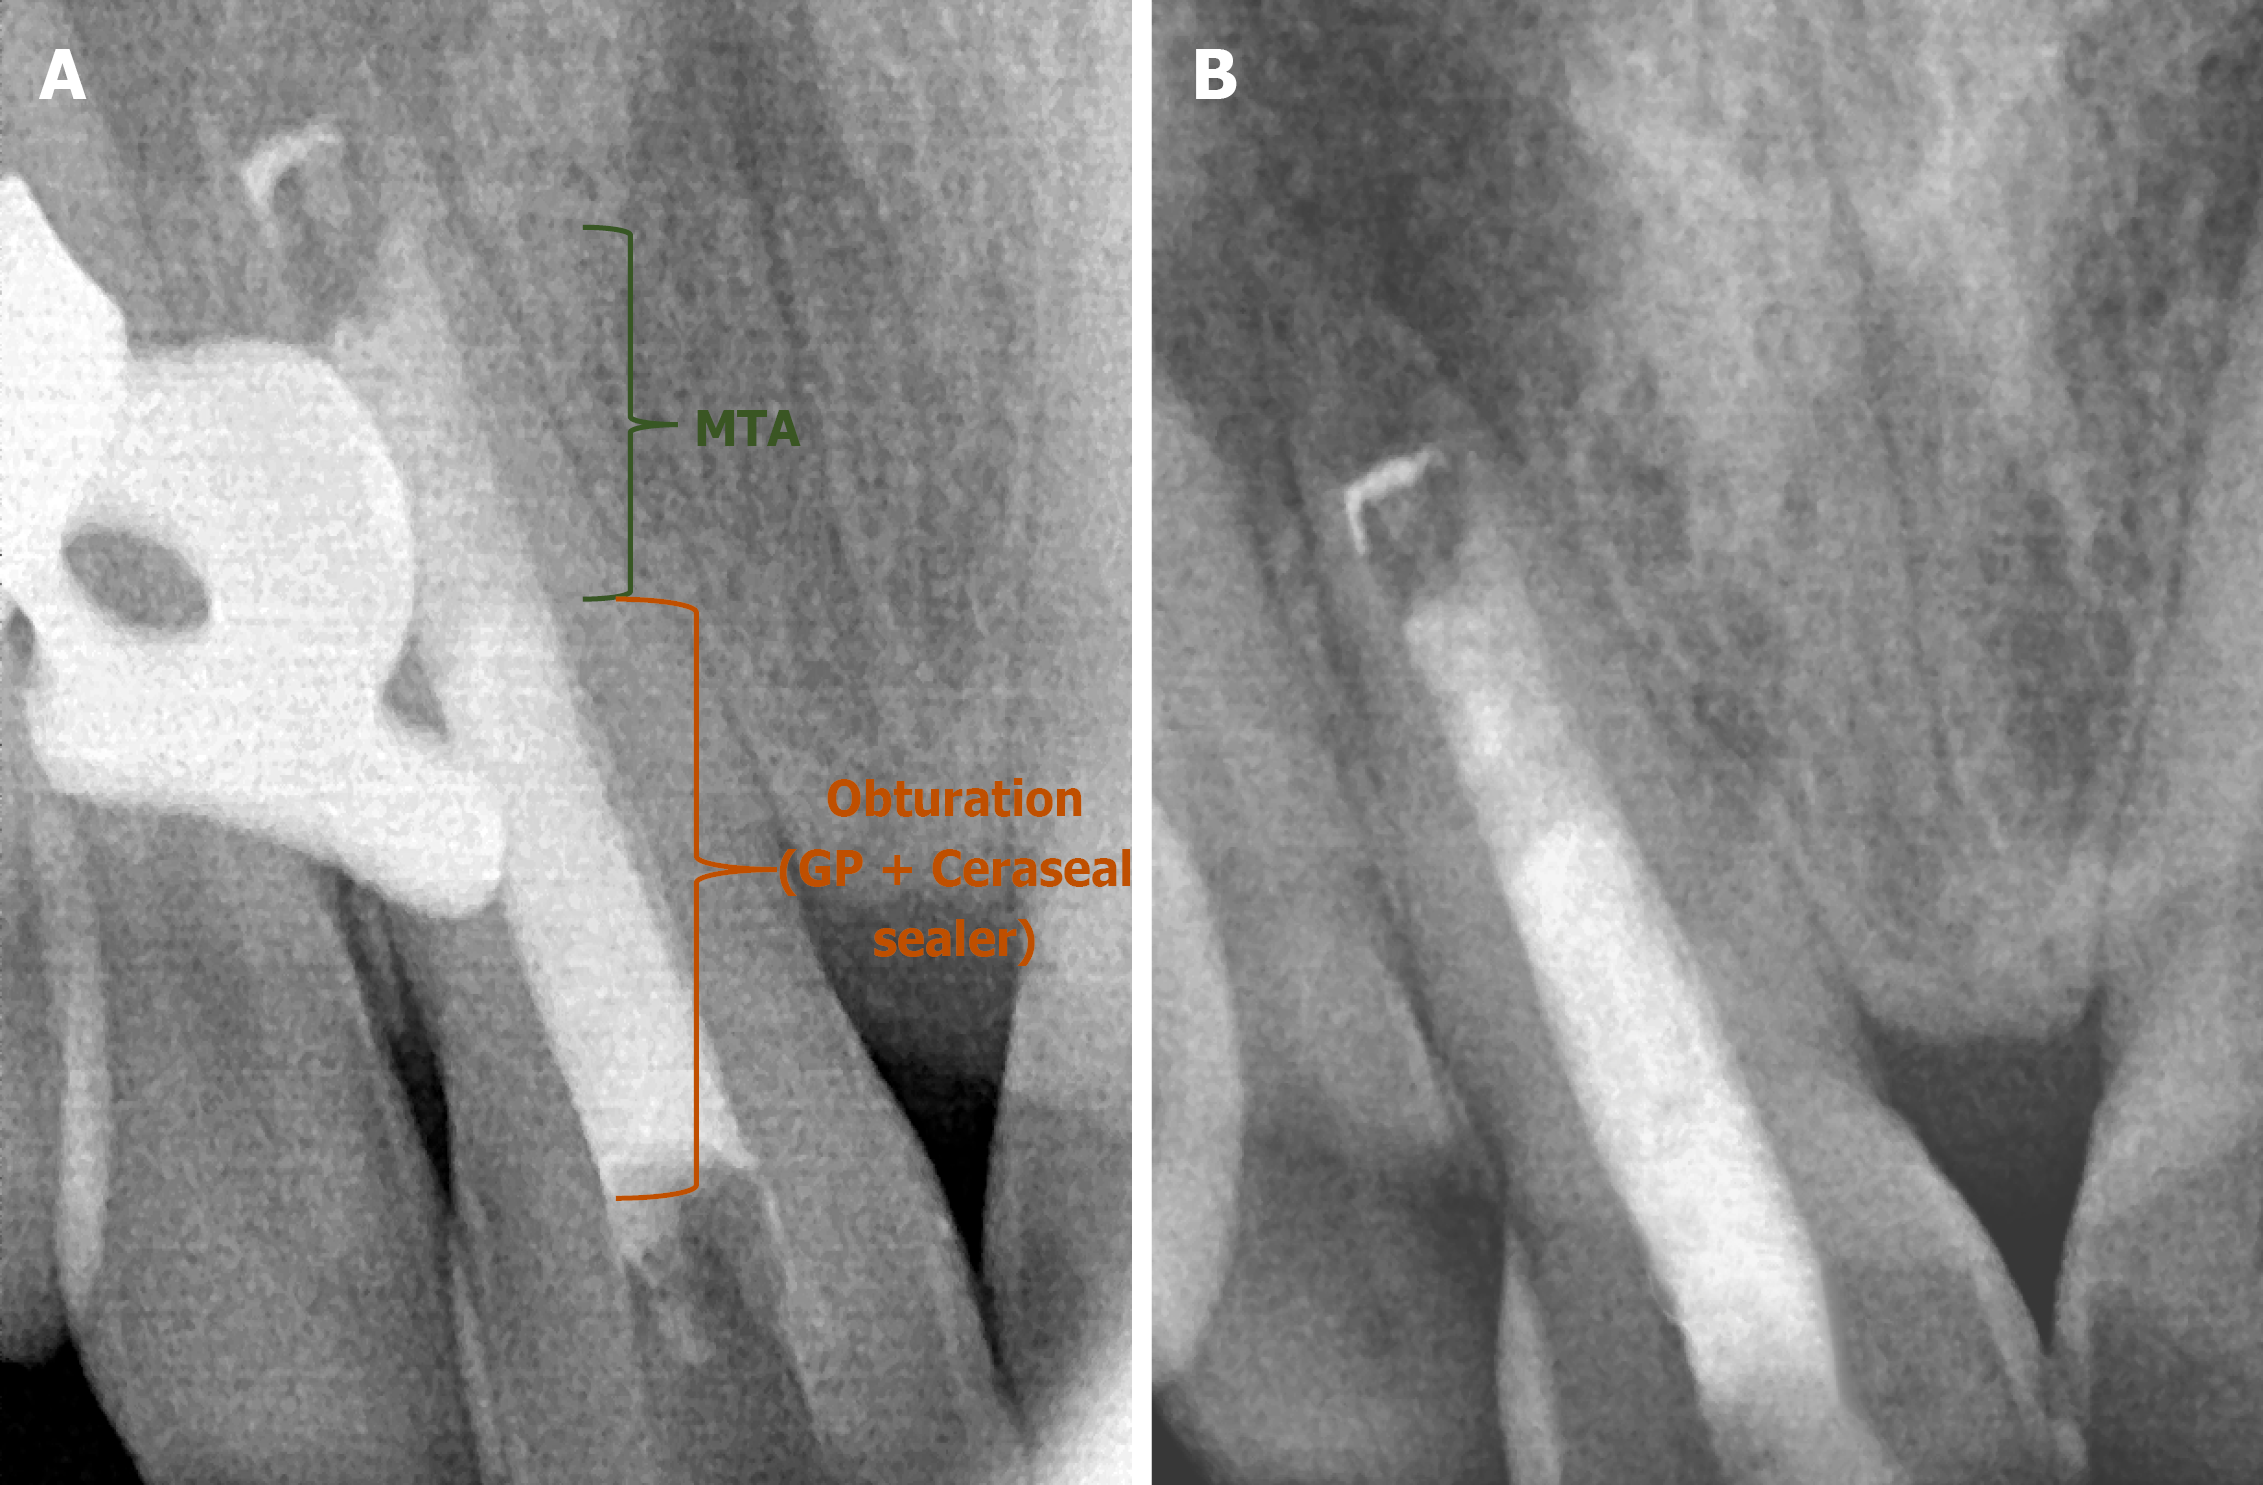

Figure 8 Shows the radiograph of the mineral trioxide aggregate plug.

A: Mineral trioxide aggregate (MTA) wrt 11; B: MTA wrt 21.

Figure 9 Shows the radiograph wrt 11.

A: Obturation; B: Post-endo composite. MTA: Mineral trioxide aggregate.